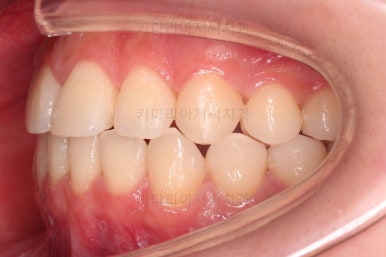

초진 시 다른 부위들 사진입니다.

약간의 주걱턱 느낌에 약간의 돌출감, 전반적인 치열의 가지런한 느낌은 나쁘지 않았지만 약간의 불량한 교합상태였어요.

다른 부분은 크게 바꾸지 말고 약간의 교합조절과 어금니 치료에 초점을 맞춰서 교정치료 계획을 잡았습니다.